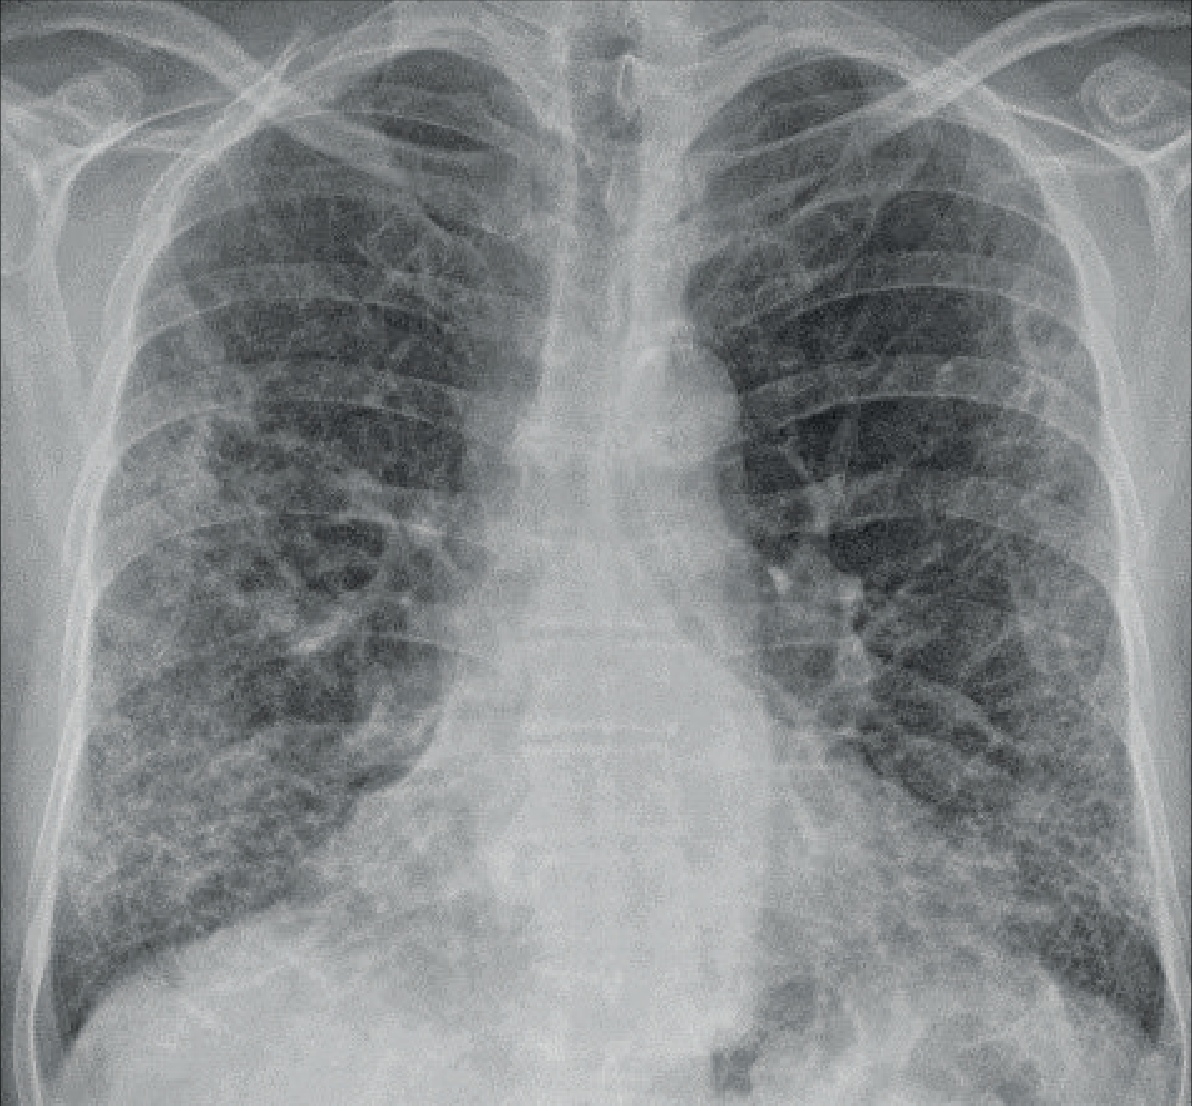

Op een röntgenfoto van de borstkas van Peter waren enkele afwijkingen in de longen te zien die kunnen passen bij bindweefselvorming in de longen.

Röntgenfoto van de borstkas

Hierbij wordt een afbeelding van uw longen gemaakt. Verdichtingen kunnen wijzen op littekenvorming.